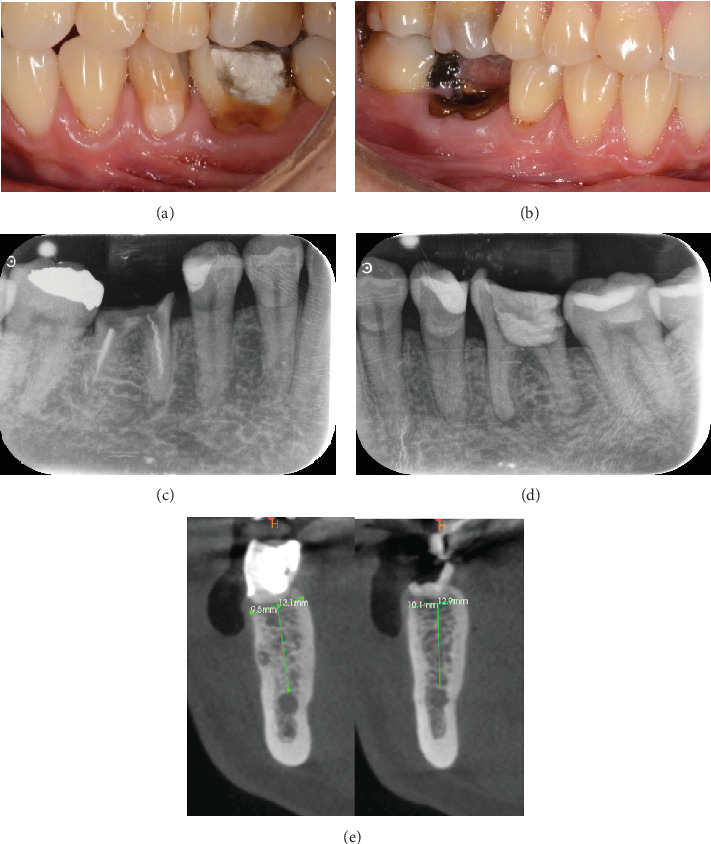

Background: The management of peri-implant tissue seeks to meet the aesthetic expectations of patients, with a smaller number of procedures that favor the development and maintenance of healthy peri-implant soft tissue. The customized healing abutment technique on immediate implants has demonstrated numerous functions for the success of restorations on implants. Objectives: The objective of the study is to analyze the biological aspects of the customized healing abutment using PEEK and flowable composite to condition the peri-implant tissues by presenting a clinical case of a patient from the oral surgery service of Pontificia Xavierian University. Case Report: A patient underwent the placement of two postextraction implants and customized healing abutments in the posteroinferior area. Discussion: This technique is aimed at maintaining the volume of keratinized mucosa and creating an emergence profile for the future prosthesis and reducing the risk of peri-implantitis. The development of healthy peri-implant soft tissues is essential to achieve the aesthetics and biological success of implant-supported restorations in all stages of healing and tissue maturation, and the abutment is essential because it allows a biological seal that protects the bone tissue. Conclusion: It was demonstrated that the use of the customized healing abutment with PEEK and flowable composite immediately after implant placement after dental extraction keeps the volume of the soft and hard tissues around the implants at the time of definitive rehabilitation.